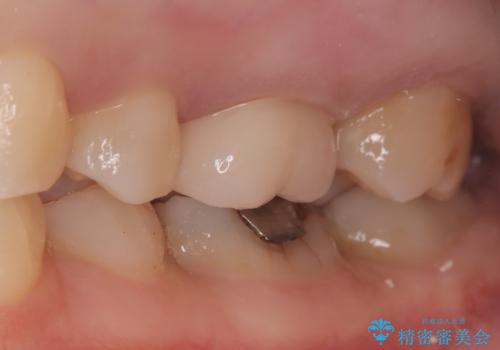

きれいな被せ物になり、患者さんにも満足していただけました。

歯牙の破折を防ぐために、セラミッククラウンにて修復しています。